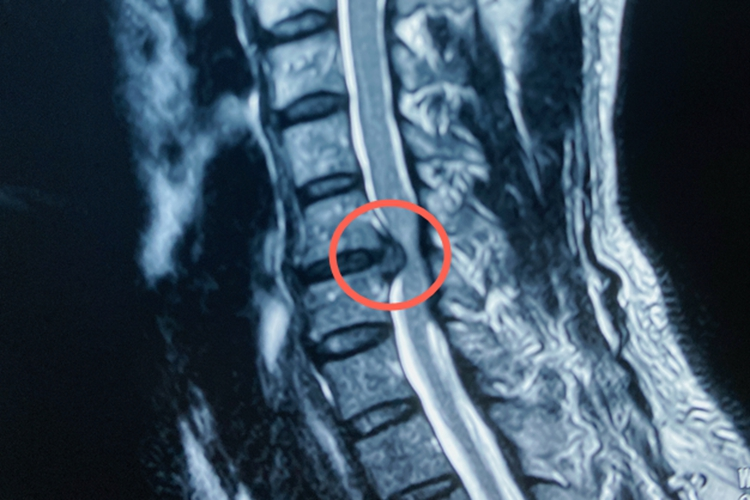

2、颈椎管狭窄:

- 颈部疼痛:多为酸痛、胀痛。

- 四肢感觉麻木:上肢可能出现放射痛,伴有放电样及烧灼样疼痛;双手可能出现麻木、无力感。

- 下肢无力:双下肢可能出现无力感,影响行走。

- 其他症状:颈部不适感,严重者可能出现截瘫、大小便失禁等。